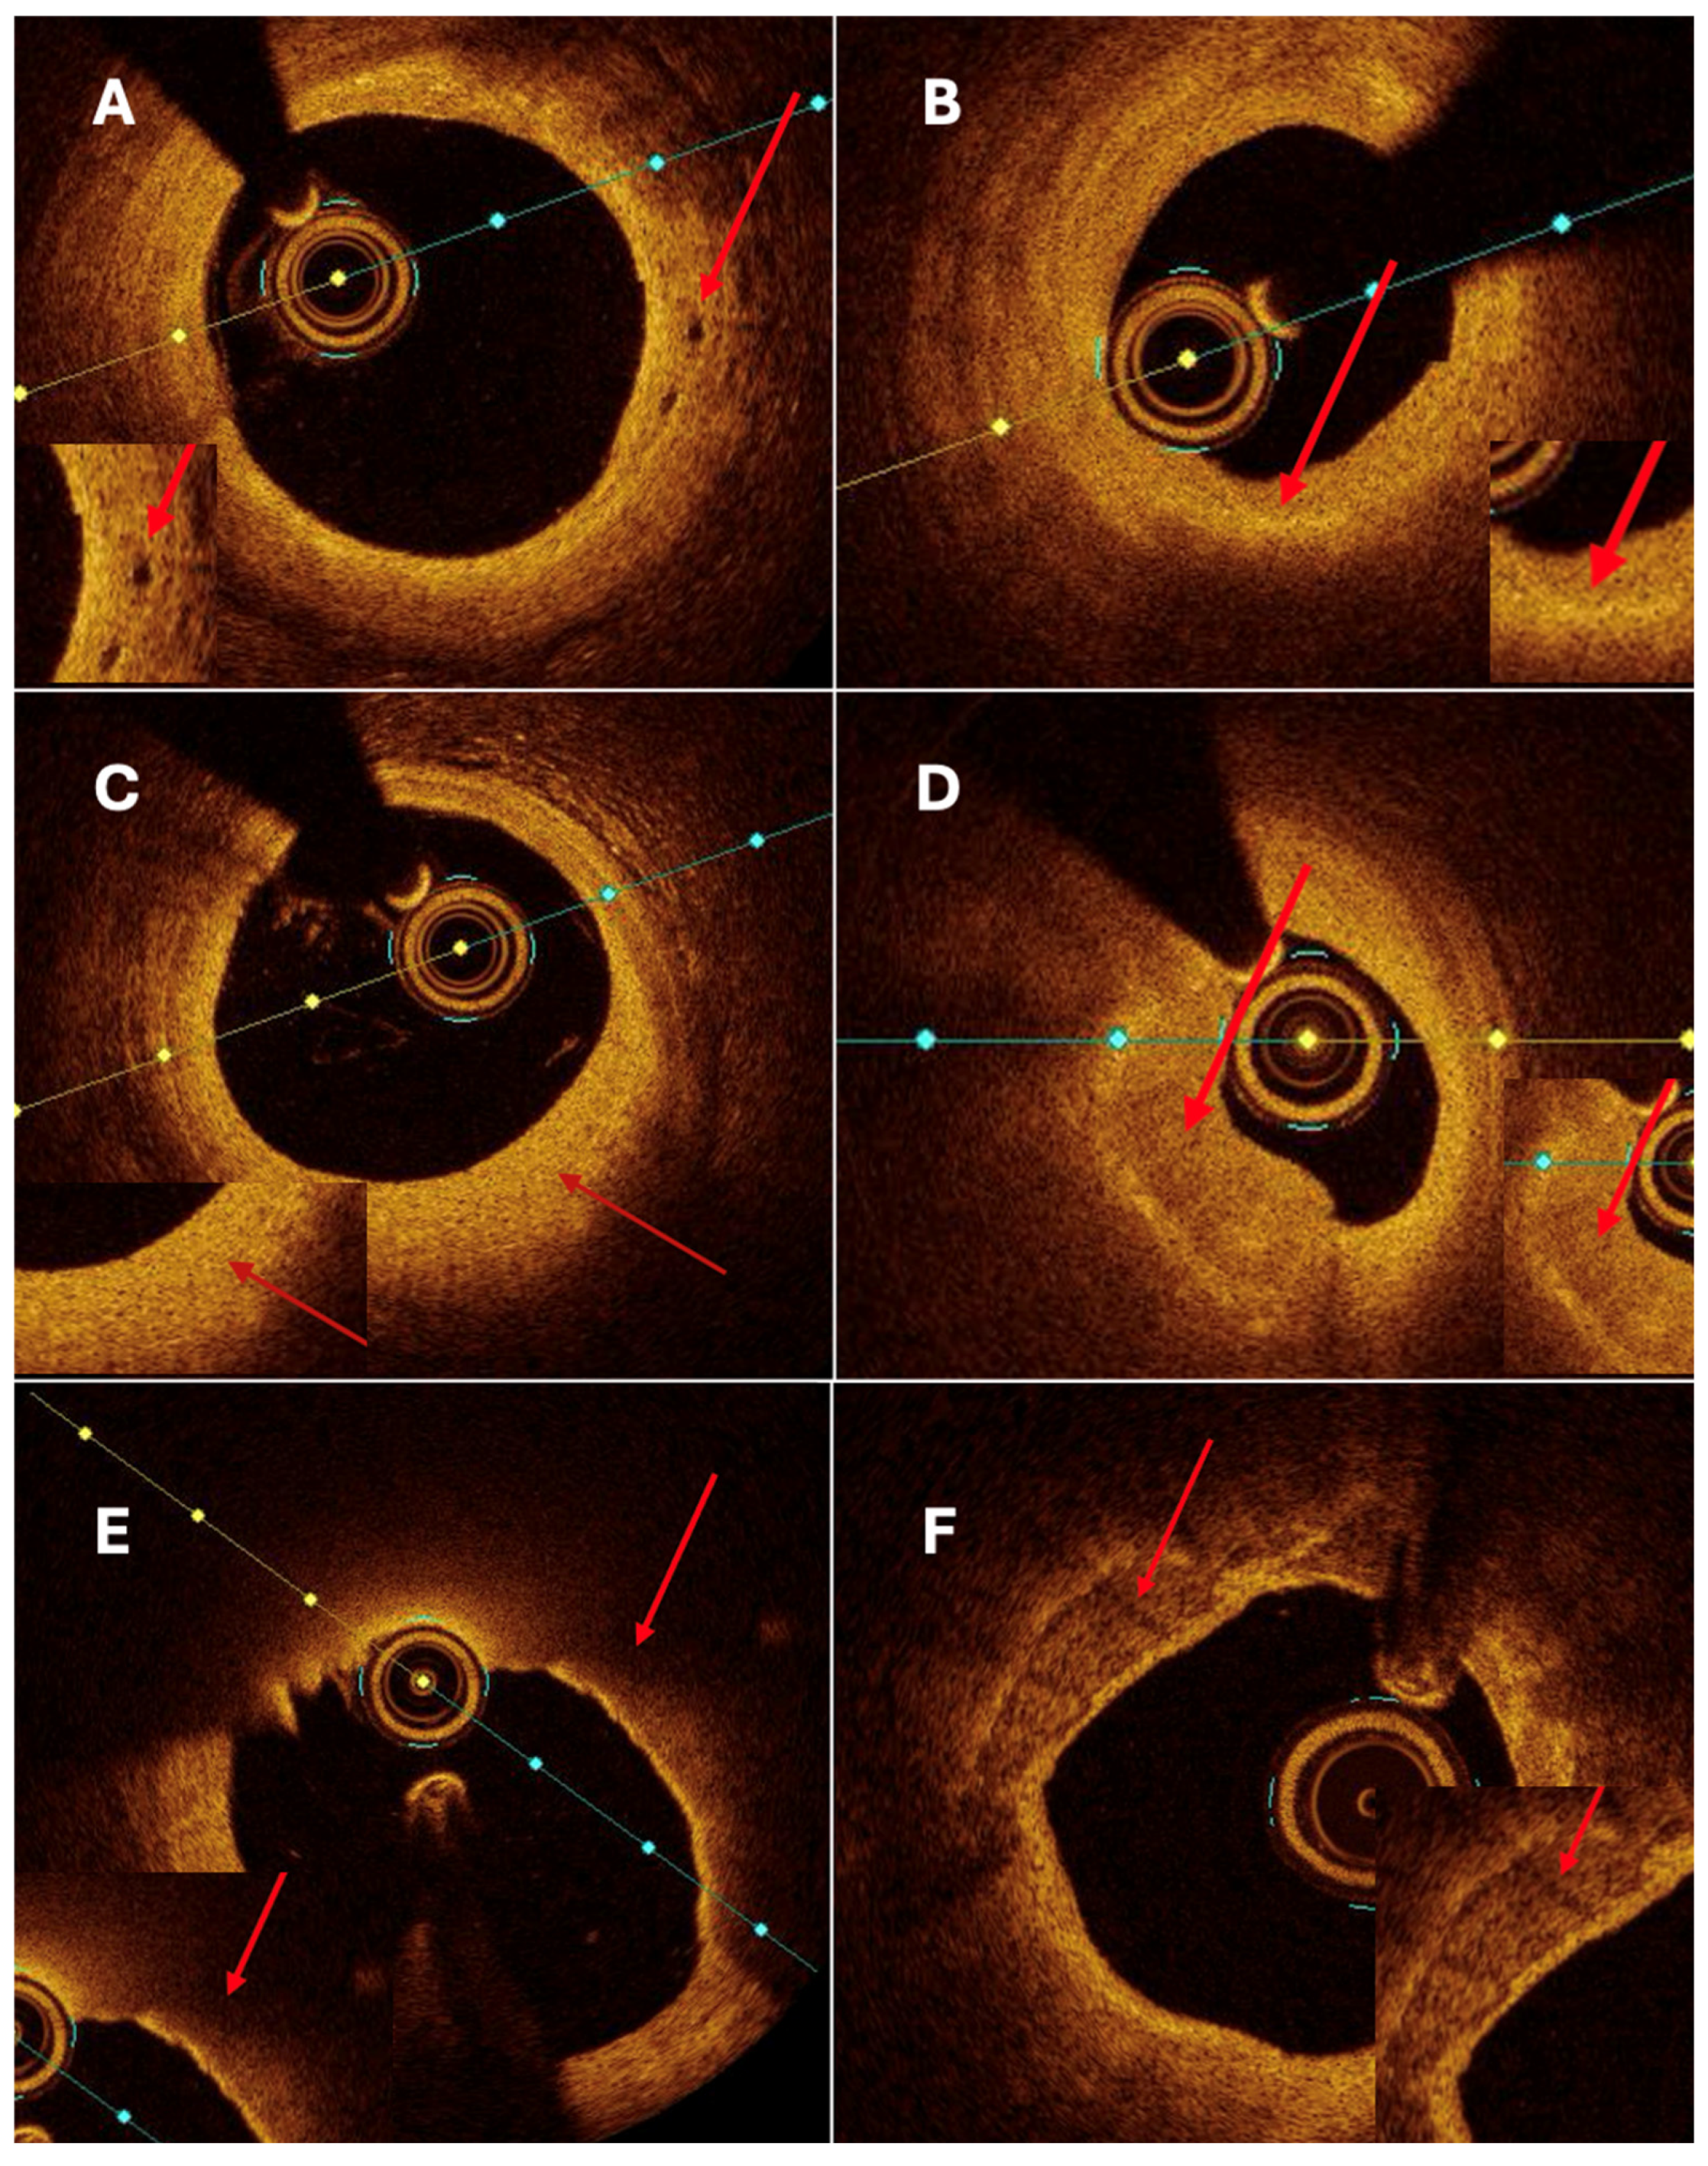

Both quantitative and qualitative OCT analysis assessed vascular remodeling. Quantitative assessment included measurements of intimal and medial thickness, as well as the calculation of the intima-to-media thickness ratio. Qualitative evaluation was based on the identification of specific morphological features, including fibrosis, calcification, cellular infiltration, neovascularization, and thrombus formation. Homogeneous areas with strong backscattering and mild signal attenuation characterized fibrosis. Calcifications were defined as well-demarcated regions with low signal intensity and minimal attenuation. Cellular infiltration was identified as signal-rich bands with strong light attenuation resulting in shadowing. Neovascularization appeared as ellipsoidal, low-signal structures consistent with microvessels (

Figure 4A). Thrombi were further categorized as white, defined by signal-rich, irregular masses with low attenuation, or red, characterized by high backscattering and strong attenuation.

No significant differences were observed for intima thickness, media thickness, intima/media ratio, calcifications (

Figure 4F), or nodules. Trends toward higher thrombus presence and macrophage infiltration were noted in non-CAAE segments, though they did not reach statistical significance.

Although thin-cap fibroatheroma (TCFA) (

Figure 4E) was more frequently identified in aneurysmal segments, fibrous cap thickness did not differ significantly between aneurysmal and non-aneurysmal regions. This apparent discrepancy likely reflects the composite nature of the TCFA definition, which incorporates plaque morphology, lipid distribution, and cap thickness in addition to cap thickness alone. In the context of coronary artery aneurysm and ectasia, TCFA may therefore represent a heterogeneous plaque phenotype within chronically remodeled vessel segments rather than a uniformly unstable lesion characterized by markedly thinned fibrous caps. These features suggest that CAAE is associated with qualitative alterations in plaque composition and vessel wall structure rather than an overall increase in plaque burden.